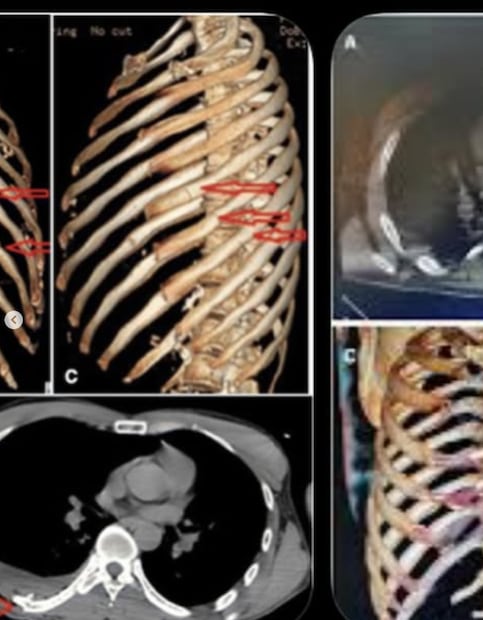

Fue en enero cuando Corey estuvo involucrado en un terrible accidente en Tulum que le ocasionó fractura en 11 costillas, así como una conmoción cerebral y lesiones faciales, por ello no pudo asistir a la boda de su padre, Rick Harrison.

En enero, Corey mostró fotos de cómo se encontraba tras el accidente y escribió:

"Estoy bastante mal, pero estoy bien. Las barras de choque son geniales. Tres noches en el hospital, once fracturas en la caja torácica. Haré un episodio en @theCoreyHarrisonshow. Lo siento, papá. Parece que me estoy perdiendo tu boda".